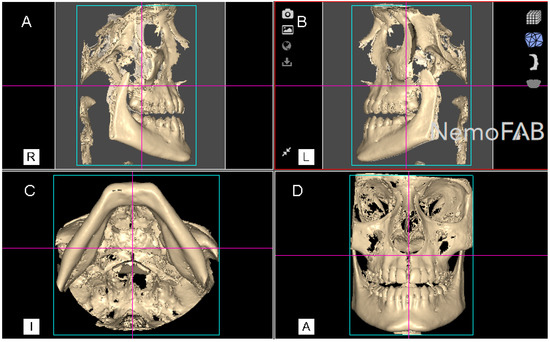

Figure 2.

(A) Right lateral, (B) left lateral, (C) bottom and (D) frontal view of the postoperative cone-beam computed tomography (CBCT) scans, aligned to the Frankfort plane and the midsagittal plane was perpendicular to the ground.